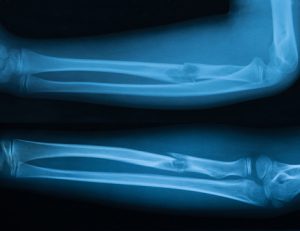

Osteonecrosis (avascular necrosis) is a disease which results from temporary or permanent blood supply to the bones. If blood cannot be supplied to the bones, they will die, causing the bone to completely collapse. If osteonecrosis occurs near the joint, then the surface of the joint can collapse as well.

Disability can occur from osteonecrosis but varies depending on which bones are affected. In a healthy individual bone breaks down and rebuilds itself, but in a person with osteonecrosis this rebuild never occurs as blood supply is lost.